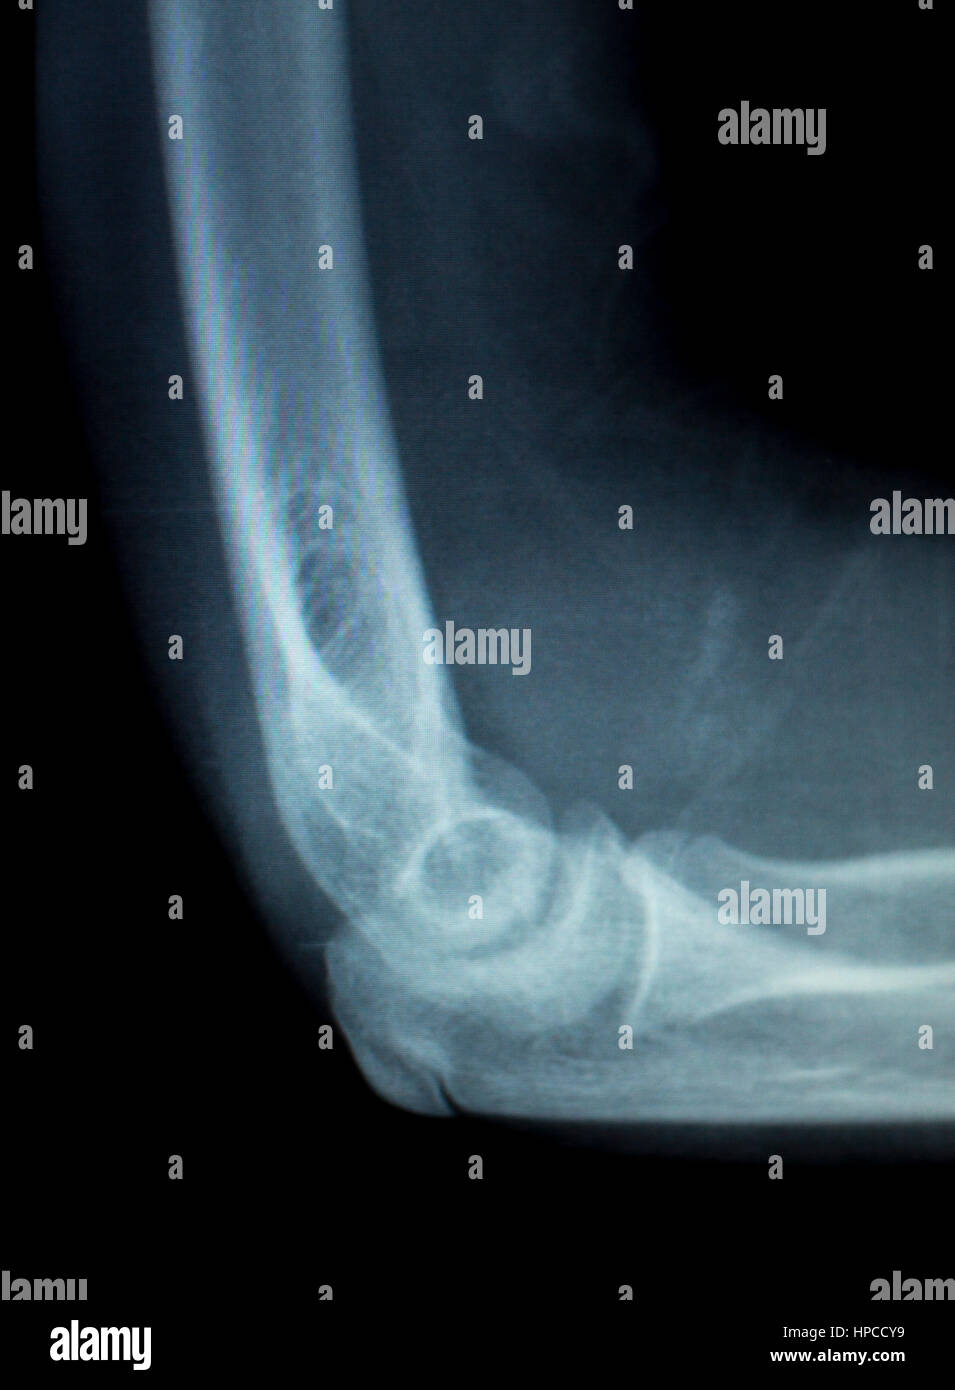

Xray Elbow Photos and Premium High Res Pictures Getty Images Tennis Elbow X Ray There is a pain subscale (0 = no pain, 10 = worst imaginable) and a. Tennis elbow (lateral epicondylitis) is swelling of the tendons that bend your wrist backward away from your palm. A procedure, such as a shot or surgery, might help tennis elbow that doesn't. Lateral epicondylitis is the most commonly encountered overuse syndrome in the elbow. Lateral. Tennis Elbow X Ray.

Elbow x ray hires stock photography and images Alamy Tennis Elbow X Ray While lateral epicondylitis is overwhelmingly encountered. A procedure, such as a shot or surgery, might help tennis elbow that doesn't. This entity is seen in patients performing repetitive wrist extension, supination, heavy lifting, or excessive gripping. Tennis elbow (lateral epicondylitis) is swelling of the tendons that bend your wrist backward away from your palm. The forearm tendons — often called.. Tennis Elbow X Ray.

Elbow x ray hires stock photography and images Alamy Tennis Elbow X Ray Lateral epicondylitis (also known as tennis elbow) is an overuse injury caused by eccentric overload at the origin of the common extensor tendon,. Tennis elbow (lateral epicondylitis) is swelling of the tendons that bend your wrist backward away from your palm. This entity is seen in patients performing repetitive wrist extension, supination, heavy lifting, or excessive gripping. The forearm tendons. Tennis Elbow X Ray.